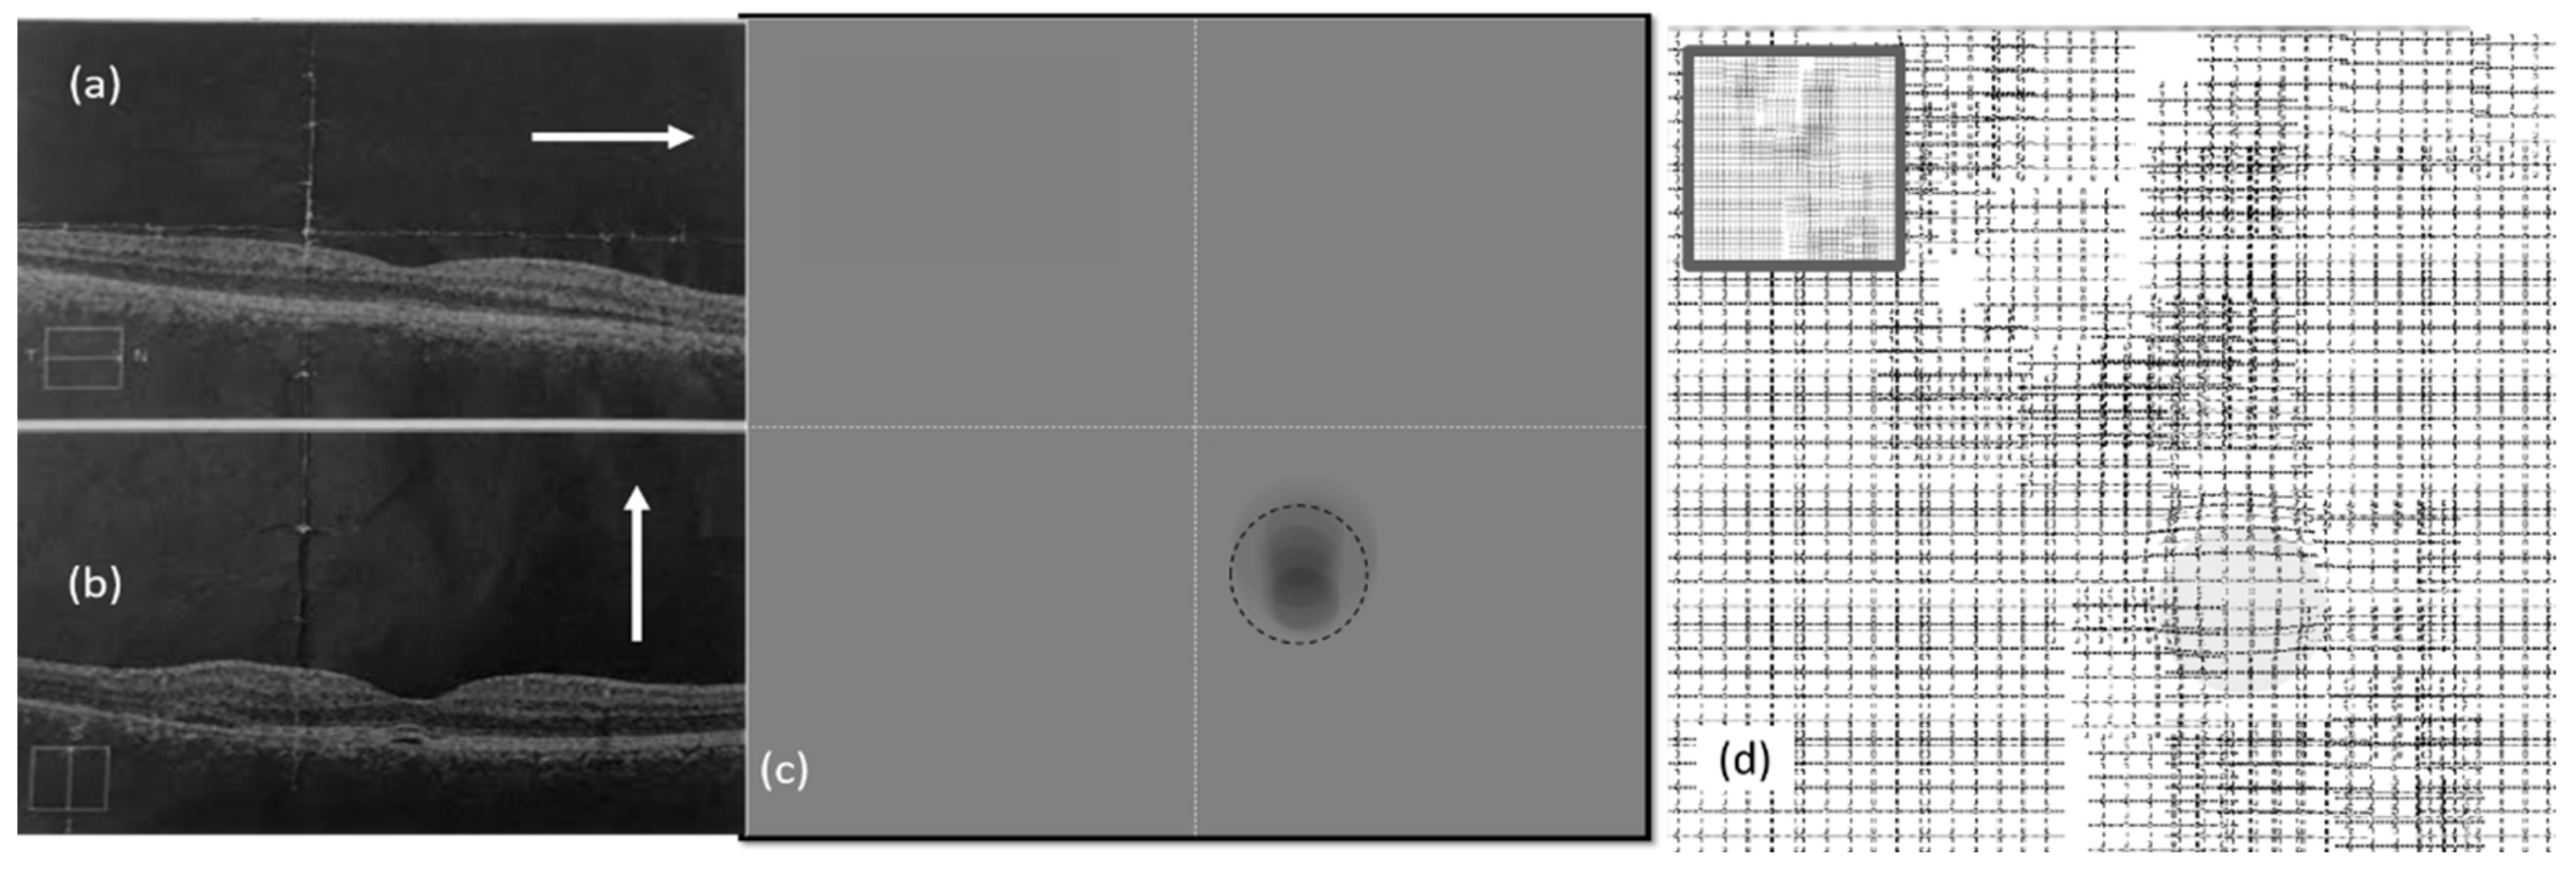

3.1. Effect of CSR in the Visual Field

3.2. Spherical Shape CSR Modeling

5.1. Simulation Results of CSR Modeling